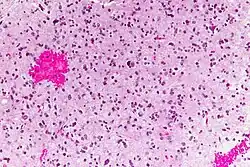

En las imágenes de RM se muestra como una lesión sólida expansiva, mal delimitada, con edema perilesional asociado y que capta contraste. Histológicamente se caracteriza por atipias nucleares, aumento de la celularidad y significativa actividad proliferativa. La neoplasia se infiltra de forma difusa en el tejido circundante, sin destruirlo por completo, de manera que las estructuras afectadas aparecen engrosadas.[3]

Las muestras de biopsia del tumor por lo general muestran una elevada densidad celular, atipias, mitosis y una significativa actividad proliferativa.[3] El origen astrocitario del tumor puede ser determinado mediante la detección de la GFAP con métodos inmunohistoquímicos. En más de la mitad de los tumores pueden detectarse mutaciones de la proteína Tp53 y de la isocitrato deshidrogenasa (IDH).[1]